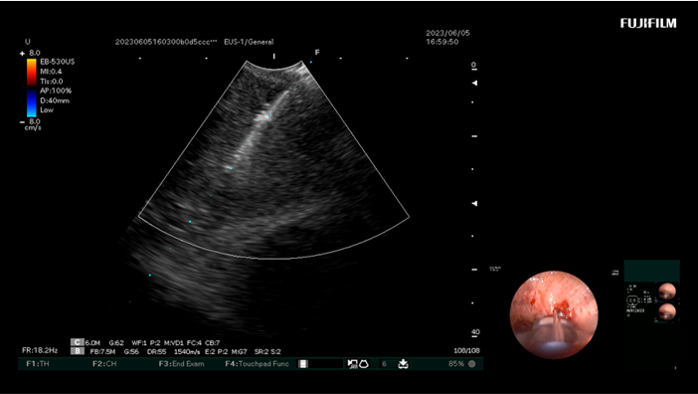

图三:支气管镜下实时显示的超声图像(黄色箭头所示为穿刺针)

结合患者病史、胸部增强CT和支气管镜结果,罗少华主任指出:患者反复呼吸困难,是间质性肺炎导致肺功能下降所致;咳嗽、咳痰情况加重与右肺占位及纵隔淋巴结转移有关,因此,及早取得病变组织进行病理检查是进行下一步治疗的关键。经呼吸内科团队讨论及充分准备后,在麻醉科的协助下,决定行超声支气管镜引导下经支气管针吸活检术,整个检测过程患者只有少量出血,送检病理结果为鳞状细胞癌,为下一步治疗指明了方向。

此次治疗的患者虽然在电子支气管镜检查及胸部CT均已明确肺占位性改变,但由于支气管内未见异常组织增生及浸润,无法取得病理组织,而超声引导下淋巴结穿刺活检,避开血管,精确定位异常淋巴结组织,因此能够减少出血的风险。